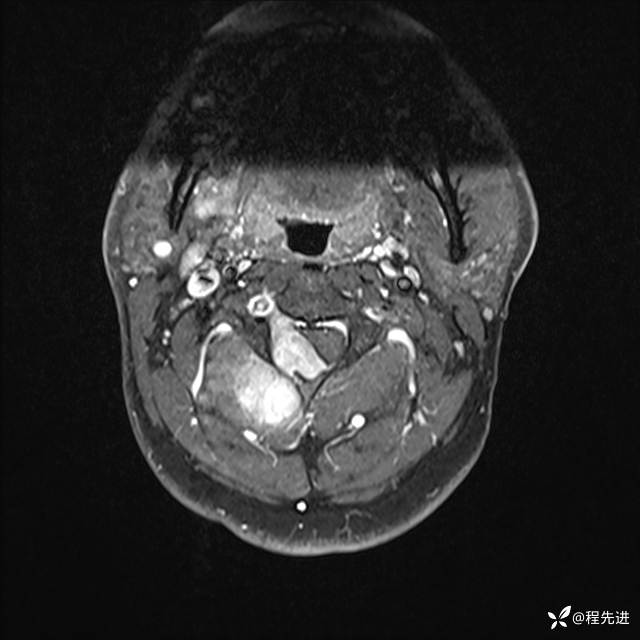

MRI平扫+增强:

T1增强: